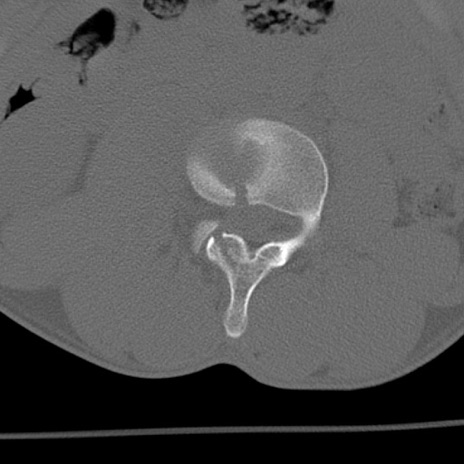

症例3 腰椎CT(横断像)

腰椎CT